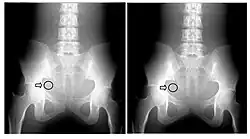

A second parameter to be derived from the transfer characteristic is the dynamic range, which expresses the range of input signals over which the image receptor is sensitive. In the case of CR, its about four orders of magnitude - see Figure 6.3, which shows its transfer characteristic in comparison to the traditional film/screen technology. The result is that under-exposure and over-exposure of regions traditionally seen radiographs are much less of an issue in clinical imaging. This feature of CR is illustrated by the radiographs in Figure 6.4.

The maximum spatial resolution of an imaging system can be readily obtained by imaging a resolution test object - an example of which is shown in Figure 6.5, panel (a). The test object consists of narrow parallel slits in a lead sheet at spacings which decrease to beyond the maximum resolution of the image receptor. The minimum spacing resolved in images is called the Limiting Spatial Resolution and can be determined to be about 3.5 line pairs/mm from the figure.